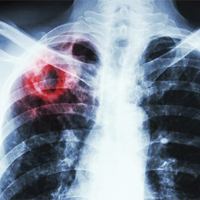

Проблема ефективного лікування туберкульозу — одна з нагальних в Україні. Однією з причин поширення мультирезистентного туберкульозу є низька прихильність пацієнтів до лікування.